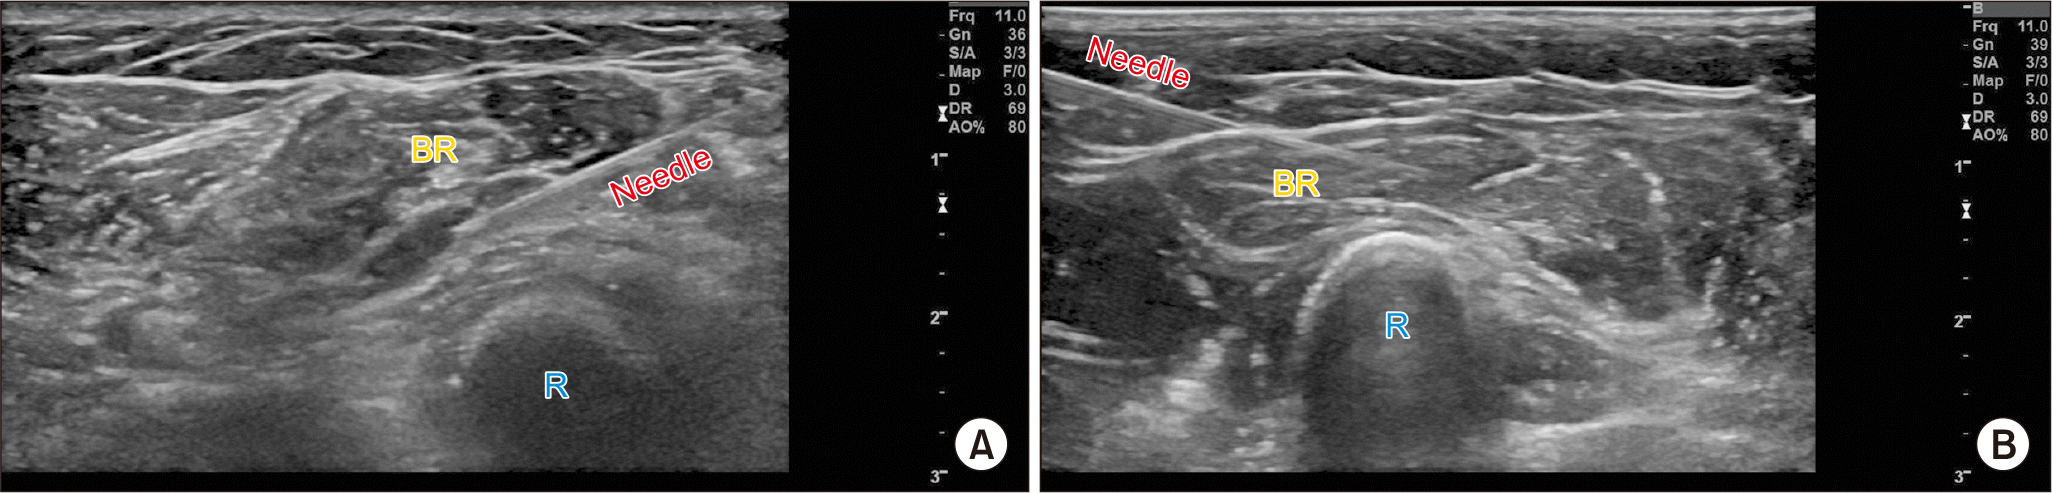

Fig. 4

Ultrasound-guided myofascial injection and intramuscular botulinum injection for brachioradialis (BR) muscle pain. (A) Ultrasound-guided myofascial injection is performed between the deep myofascium of the BR above the radius (R) bone. (B) Ultrasound-guided intramuscular injection using 10–20 IU of botulinum toxin A is performed.